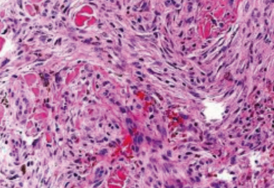

Dermatofibromas are often categorized by their histopathologic characteristics. Common subtypes include cellular, aneurysmal, epithelioid, atypical, clear, and palisading. Subcutaneous involvement varies depending on the histologic pattern. For instance, hyperkeratosis and basal layer pigmentation typically occur in the cellular and lipidized variations.2 However, different architectural patterns can co-exist within a singular lesion.8 On histology, fibrous histiocytomas will appear as interlacing fascicles of spindled cells, with varying degrees of fibroblasts, macrophages, and lymphocytic infiltrate. The spindle cells may also take on a “storiform” pattern, appearing as a multicentric swirl with elongated nuclei.6

Distinguishing the hemosiderotic type of dermatofibromas from the aneurysmal type can be a challenge and some authors consider these entities to be a spectrum of the same variant (Figure 2 and Figure 3). Hemosiderotic dermatofibromas lack large blood-filled spaces but they also contain hemosiderin and giant cells and are associated with amphophilic cytoplasm, oval nuclei, and collagen trapping.11 Histologically, aneurysmal variants of fibrous histiocytomas will appear as fibroblastic, histiocytic cells with blood-filled spaces. Multinucleated giant cells, foamy cells, and hemosiderin-laden macrophages may also appear on histology.12 As previously mentioned, it is essential to be able to distinguish benign dermatofibromas from more concerning pathologies like dermatofibrosarcomas, which are malignant tumors that contain uniform, bland spindle cells on histology.13